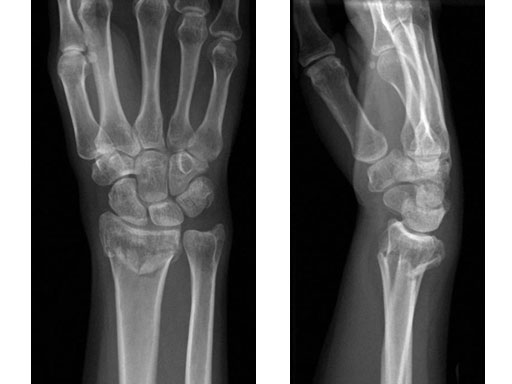

36-year-old female fell down on a meadow.

Fig 1ab Preoperative x-rays.